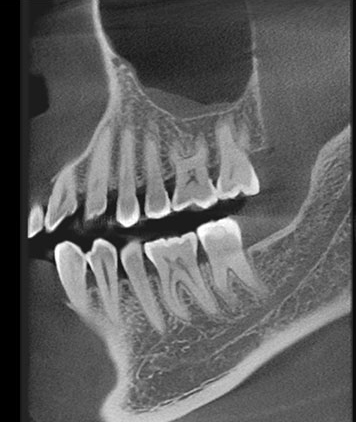

- Khám và chẩn đoán: Bác sĩ sẽ thực hiện khám răng miệng và chụp X-quang để xác định mức độ viêm nhiễm của tủy răng.

Tại Nha Khoa Bảo Tồn Cửu Vân sử dụng máy X-quang CBCT 3D đến từ thương hiệu Ray với độ chính xác và hình ảnh sắc nét, giúp cho việc chuẩn đoán và điều trị có tỷ lệ thành công cao.